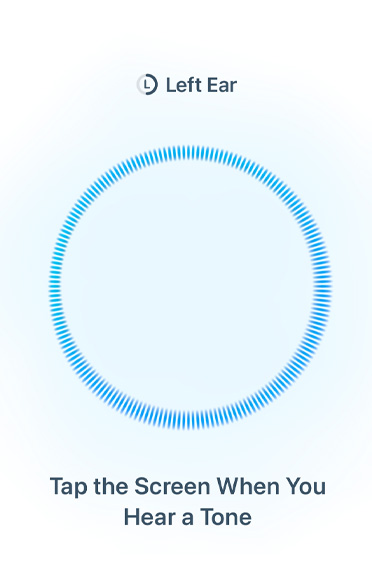

Hearing Health

Check, aid, and help protect your hearing.

AirPods Pro 3 bring improvements to the world’s first end-to-end hearing health experience.6 Now you can take a scientifically validated Hearing Test in a broader range of background conditions. The Hearing Aid feature adds improved voice clarity, automatic Conversation Boost,7 and 67 percent more battery life in Transparency on a single charge.8 And active Hearing Protection helps prevent exposure to loud environmental noise.21

Hearing Test and Hearing Aid.

With a better fit and increased noise cancellation, you can now take a scientifically validated Hearing Test in a broader range of everyday background conditions — from the comfort of your home. And if you have mild to moderate hearing loss, you can use the improved Hearing Aid feature wherever you go.6